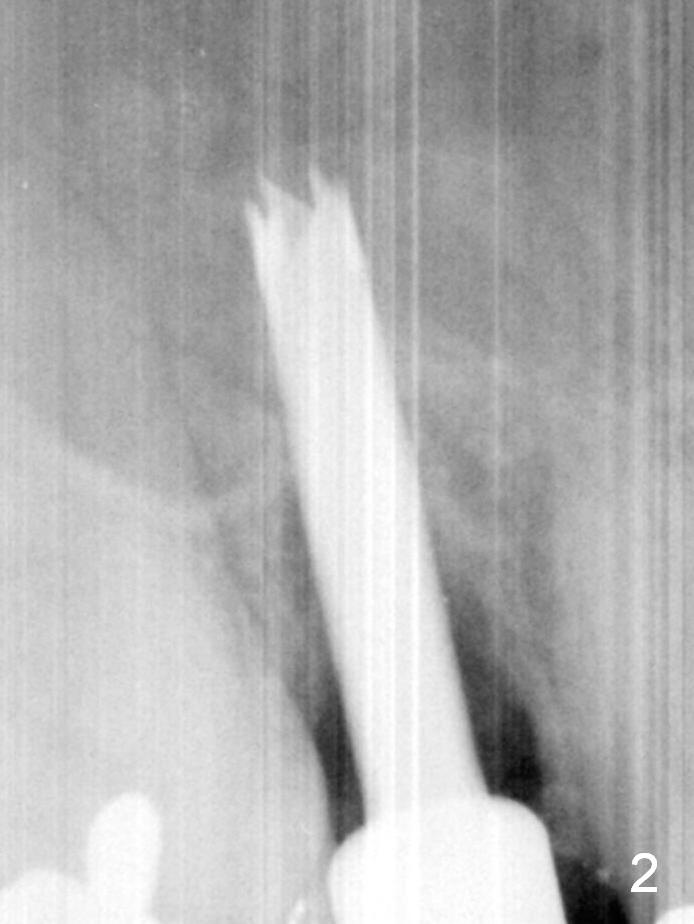

To prevent sinus lift related sinusitis, a shorter implant is going to be placed (Fig.1), approximately 2 mm beyond the apex.  Following extraction, the buccal plate (Fig.3a (coronal section): B) is not only ~ 2 mm shorter than the palatal one (P), but also thinner.  Since the bone density of the palatal plate is higher, without osteotomy an implant is less likely placed in the middle of the socket (S (Fig.1); Fig.3b) than buccal (Fig.3c).  Therefore drills are used to form osteotomy in the apical 1/3 of the palatal slope (Fig.3d (red arrow); SM: sinus membrane).  When 3.3 mm Magic Drill (MD) is in place (Fig.2), the distal surface of the sinus septum is perforated without air leakage.  Demineralized allograft (.0125-.085) is placed for sinus lift (Fig.4 *) prior to placement of 4.5x11 mm implant with ~ 30 Ncm.  The implant is slightly buccal to the ideal position indicated in Fig.3e (curved blue line: sinus lift).  A 4.5x4(2) mm pair abutment is placed for an immediate provisional to hold mineralized allograft in the remaining socket gaps (Fig.4 arrowheads, .5-1.5 mm).  A 9 mm implant may avoid sinus floor perforation on the distal slope of the 2nd premolar.  The osteotomy should have been established initially as mesial as possible.  In fact the patient has nasal hemorrhage while sneezing for the first 2 days postop.  Although he complains of pain buccal to the implant, the gingiva appears to heal 7 days postop (Fig.5).  The distobuccal papilla appears to be displaced somewhat.  Raising mucoperiosteal flap is most likely associated with postop pain and esthetic compromise.  The implant appears to have osteointegrated 5 months postop (Fig.6).  A 4.5 mmx15° 3 mm cuff angled abutment is placed for final restoration.  The distolingual portion of the implant is supported by the regenerated bone 3 years post cementation (Fig.7,8).  There is no bone loss 4 years 2 months post cementation (Fig.9,10).